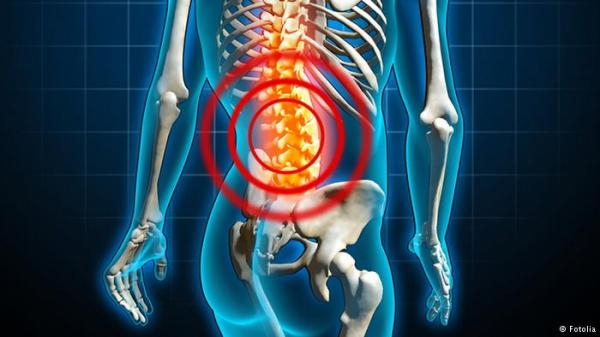

ويرى الأطباء أن تقويس الظهر يعتبر من هذه العادات غير الظاهرة حيث تزيد طريقة الوقوف والجلوس الخاطئة من حجم الخصر وتقلل من حجم الصدر. ويعلل المختصون عادة تقويس الظهر بأنها تعود إلى ضعف عضلات جذع الإنسان والإرهاق المزمن مما يجسد تلك الأحمال التي تؤدي إلى انحطاط الكتفين. ويدل تقوس الظهر عند بعض الأشخاص على نقص في تقييم الذات وعدم ثقة بالنفس

كما يؤثر الجلوس بطريقة وضع الرجل على رجل أخرى سلباً على هيئة الإنسان لأن الإفراط في الجلوس بهذه الطريقة يؤدي إلى خلل في الدورة الدموية والتيار اللمفي مما يزيد مخاطر توسع الأوردة والأوديمة والالتهاب الخلوي، طبقاً لما ورد بموقع روسيا اليوم